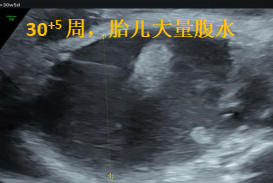

37岁的m女士,这是她的第三个宝宝,从怀孕到30周,一路平顺走来。直到孕30 3周时,在当地做胎儿超声提示“胎儿腹盆腔大量积液”,这个陌生的医学术语曾让全家彻夜难眠。

次日,她们来到了昆明安琪儿妇产医院产前诊断中心谢敏医生的门诊,在与超声科吴云萍医生的共同评估下,发现宝宝腹腔内大量积液,肠管受压挛缩,但经过详细地畸形排查,并没有发现其他的结构异常或生长发育方面的问题。通过充分的遗传咨询和分析,m女士一家决定竭尽全力救治与她已经共度了200多天的宝宝。